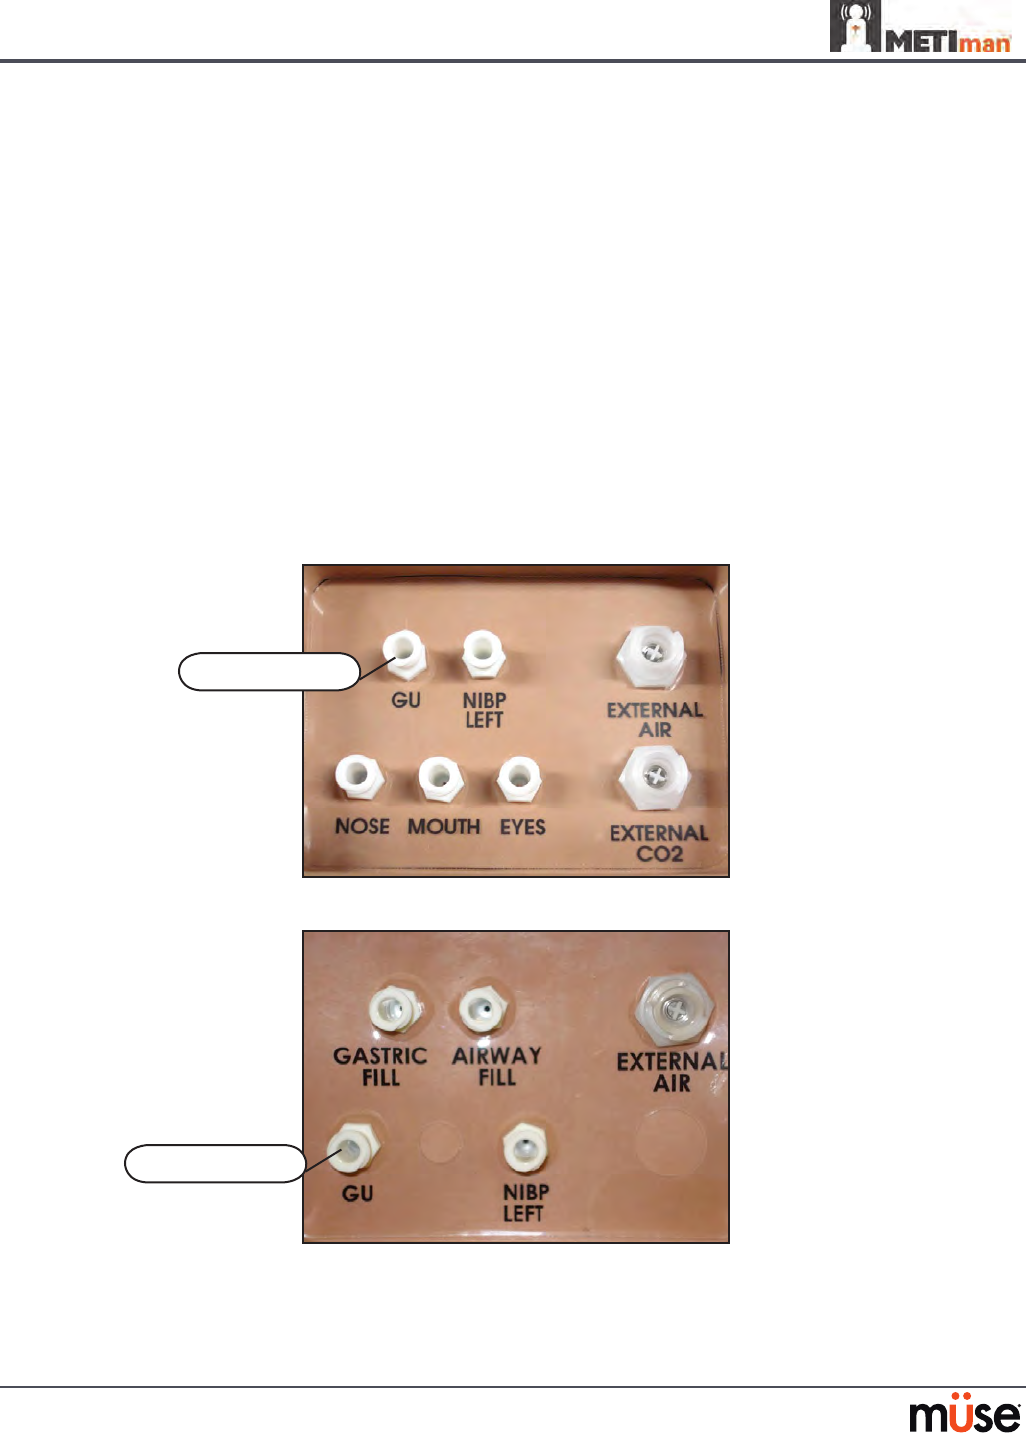

Head Secretions (Prehospital Only)

Secretions of the eyes, nose and mouth are manually controlled with a gravity feed.

NOTE: An IV bag is needed for each site in use.

To use the head secretion features:

Using a 60 mL syringe, prime the line of the desired secretion by injecting uid

1.

into the NOSE, MOUTH or EYES port on METIman’s left shoulder until uid

emerges from the secretion sites.

Set up the IV pole near the simulator.

2.

Fill an IV bag with the clinically appropriate uid. Use distilled water only, with 3.

food coloring, if desired.

Hang the IV bag on the IV pole.

4.

Ensure the roller clamp is closed and insert the IV spike into the IV bag.5.

Connect to the simulator by attaching the end of the IV spike set tubing to the 6.

NOSE, MOUTH or EYES port on the simulator’s left shoulder. (Repeat for each site

necessary.)

METIman Prehospital’s Left Shoulder

Open the clamp and allow uid to ow into the simulator. 7.

Keep the IV bag attached. Adjust the ow rate manually using the roller clamp.8.

NOTE: Cleanup is very important when using simulated uids. Please refer to the Care and

Maintenance section for directions on uid removal.

The NOSE,

MOUTH and

EYES ports

129

Airway Secretions (Nursing Only)

METIman Nursing allows for suctioning of uids from the airway using a manual feed. Ensure

all uids have been removed from previous uses before each new use to prevent overlling.

Tracheostomy Suction

To use the airway secretion feature, inject up to 40 mL of clinically appropriate colored uid

into the AIRWAY FILL port on METIman Nursing’s left shoulder.

METIman Nursing’s Left Shoulder

The trachea is now ready to be suctioned. Using the proper clinical technique, insert the

suction catheter (14 Fr) until resistance is encountered at the bifurcation. Withdraw and apply

suction. Fluid can be suctioned over a distance of approximately 4 cm distal to the bifurcation.

NOTE: Use only distilled water with food coloring, if desired.

NOTE: Cleanup is very important when using simulated uids. Please refer to the Care and

Maintenance section for directions on uid removal.

The AIRWAY

FILL port

Genitourinary System

METIman may be congured with either male or female genitalia, either of which allows for

the insertion of a urinary catheter. The genitourinary system also provides for the excretion of

urine.

Urinary Catheterization

Catheterize the simulator using a standard 16-Fr urinary catheter lubricated with silicone spray.

Urinary Catheterization

The bladder for the simulated urine is accessed directly via the urethra.

Simulating Urine Output

METIman allows urinary catheterization and simulation of urinary output. Ensure all uids have

been removed from previous uses before each new use to prevent overlling. Please refer to the

Care and Maintenance section for directions on uid removal.

To simulate continuous urinary output:

Set up the IV pole near the simulator.

1.

Fill an IV bag with the clinically appropriate uid. Use distilled water only, with food 2.

coloring if desired.

Hang the IV bag on the IV pole.

3.

Ensure the roller clamp is closed and insert the IV spike into the IV bag.4.

Connect to the simulator by attaching the end of the IV spike set tubing to the 5. GU

port on the simulator’s left shoulder.

METIman Prehosptial’s Left Shoulder

METIman Nursing’s Left Shoulder

The GU port

The GU port